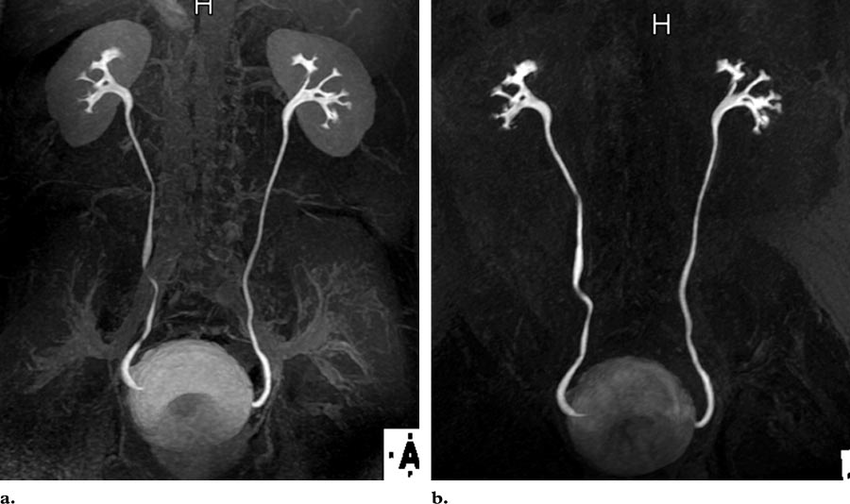

Интерпретация результатов урографии осуществляется урологом. На основании изучения снимков он дает заключение о состоянии почек и других органов выделительной системы, в котором описывает выявленные отклонения от нормы. Экскреторная урография показывает:

- анатомическое положение, структуру почек;

- состояние чашечно-лоханочного аппарата почек, его структуру, форму;

- состояние мочеточников по отдельности и в сравнении, их размеры, анатомическое положение, деформации, скорость продвижения по ним контрастного вещества;

- состояние мочевого пузыря, его размеры, локализацию, характеристики стенок.